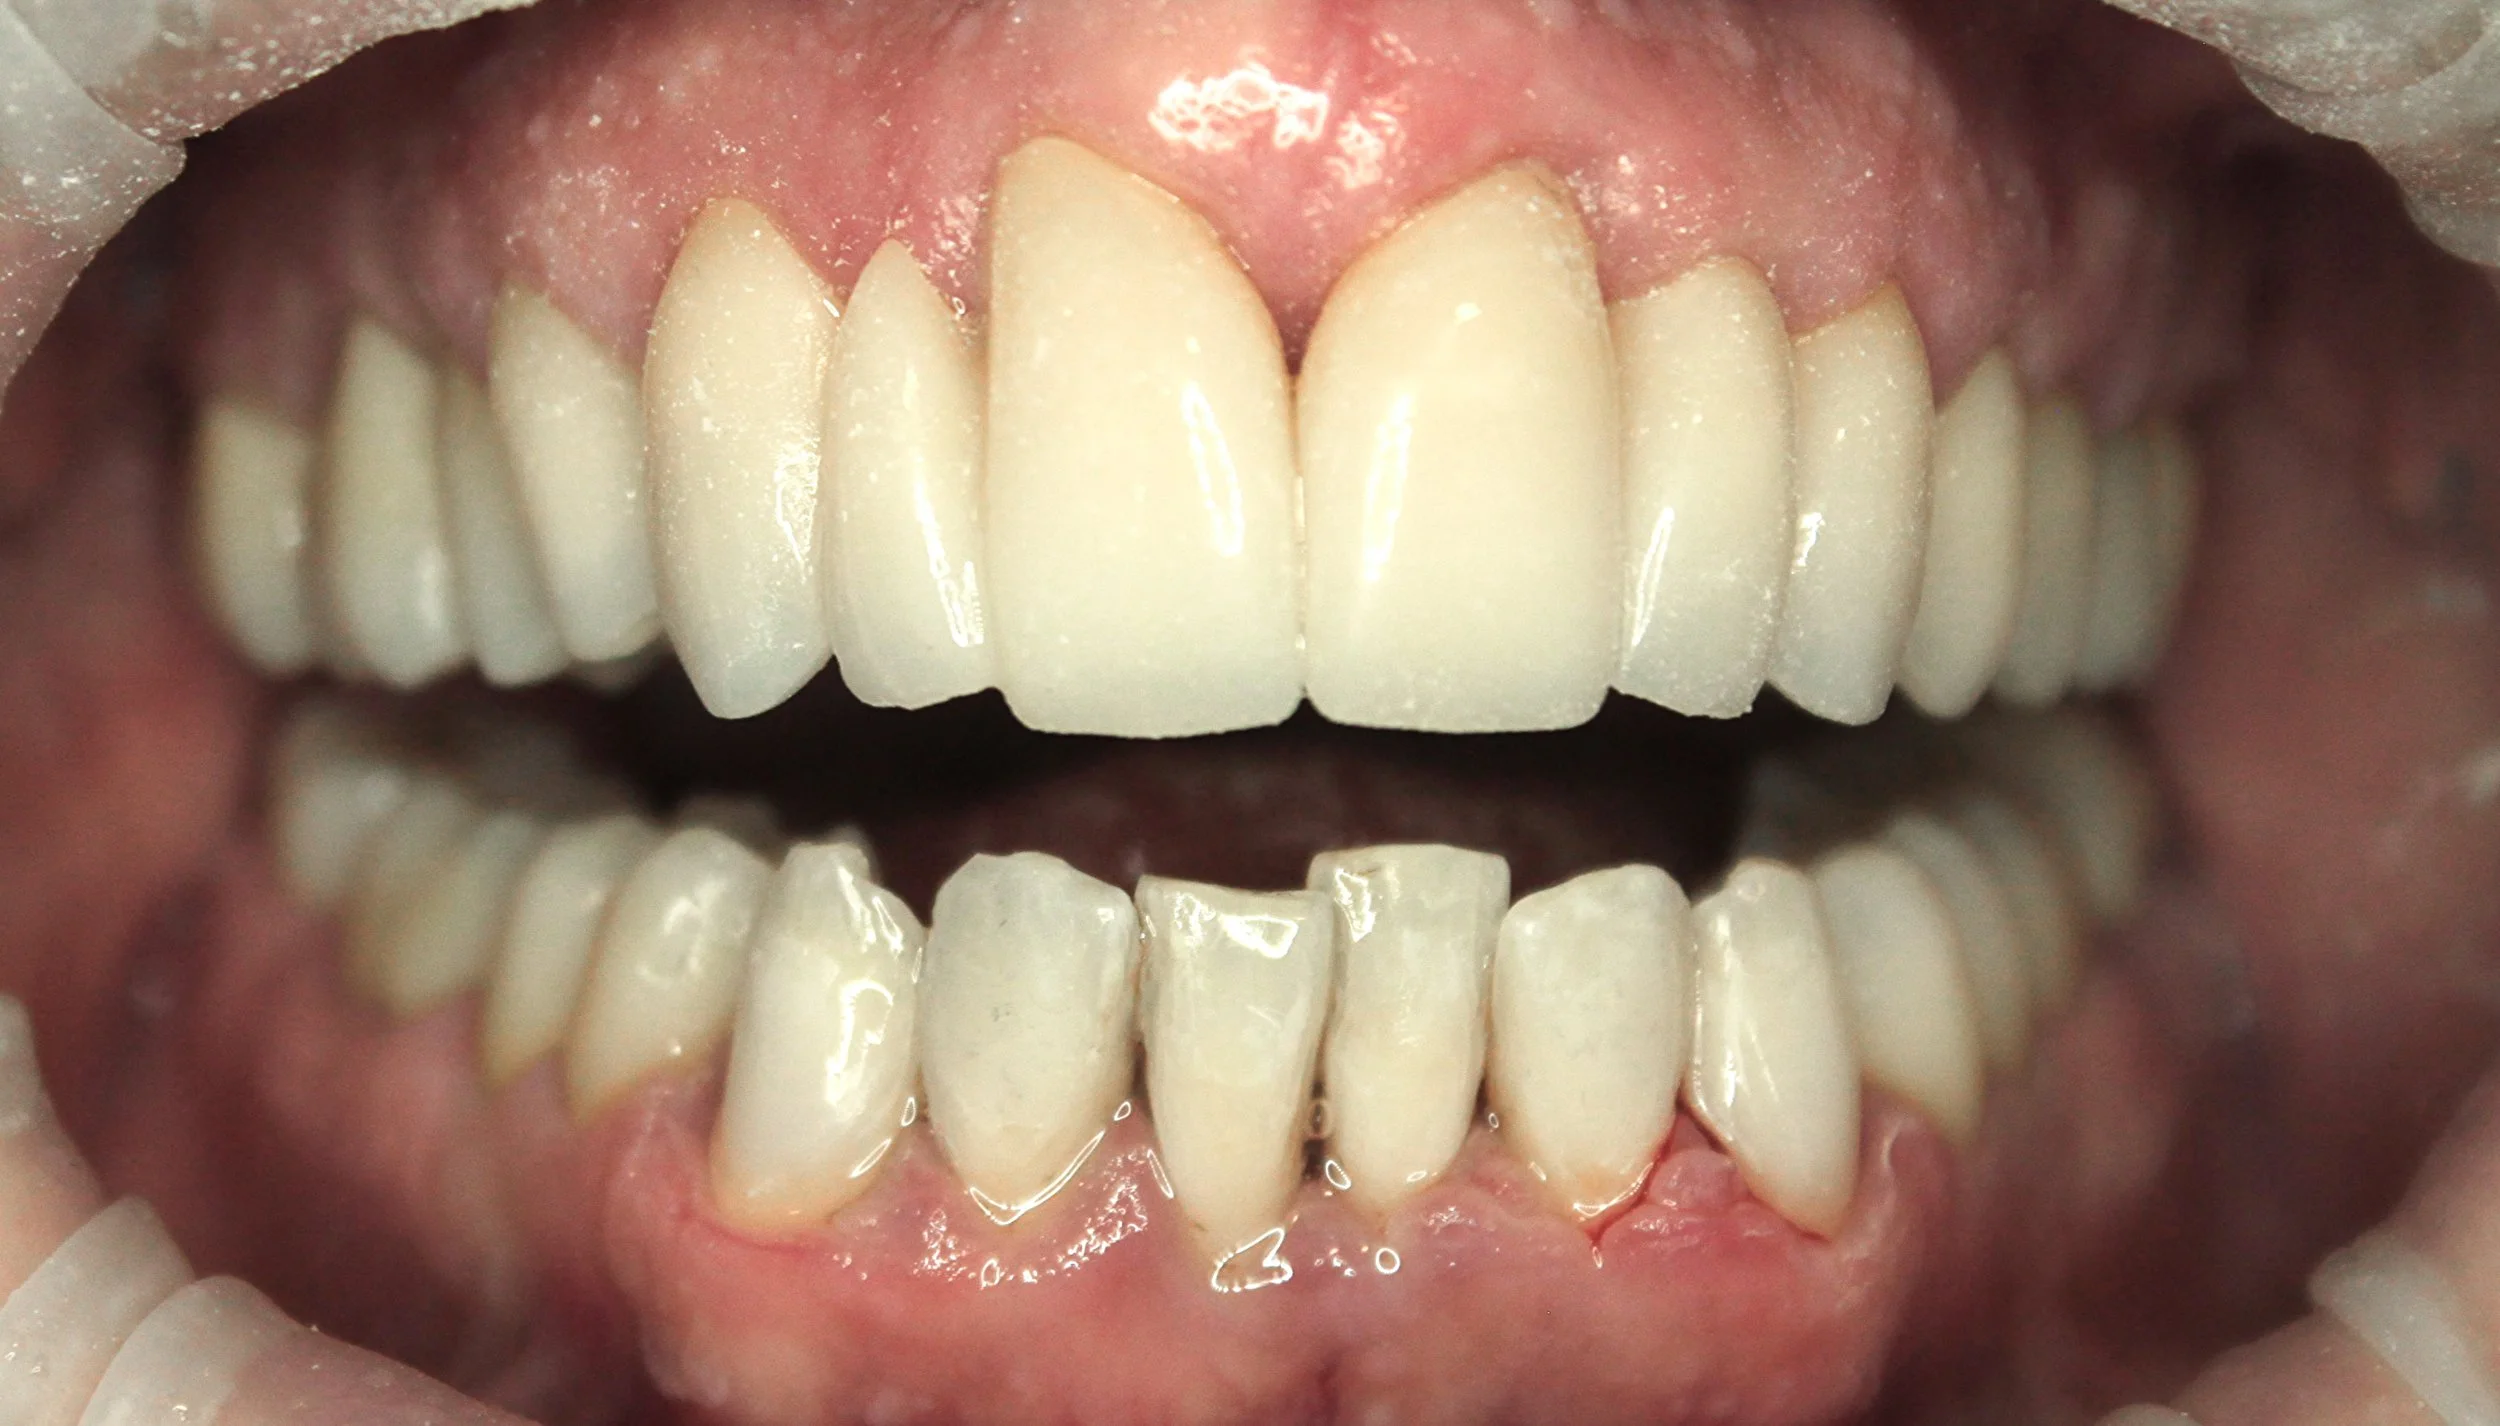

AVANT / APRÈS